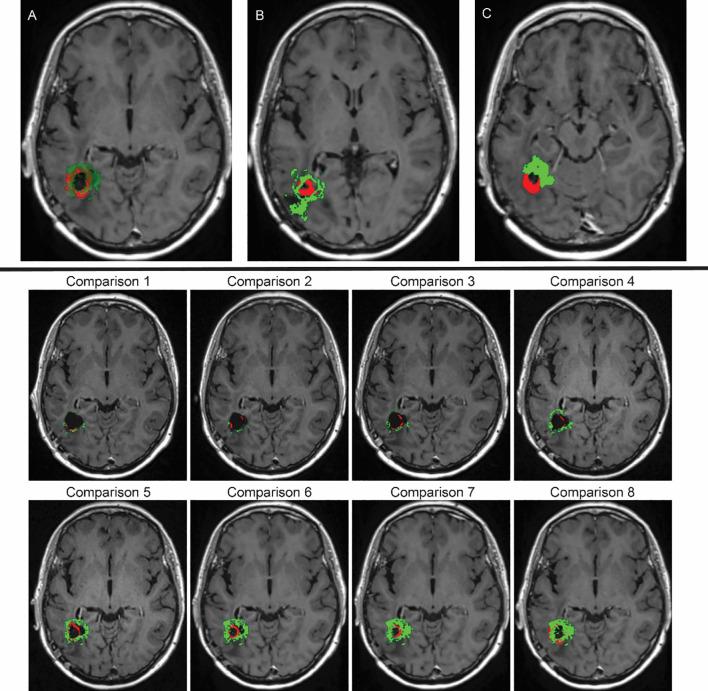

Glioblastoma multiforme (GBM), the most aggressive primary brain tumour, exhibits low survival rates due to its rapid growth, infiltrates surrounding brain tissue, and is highly resistant to treatment. One major challenge is oedema infiltration, a fluid build-up that provides a path for cancer cells to invade other areas. MRI resolution is insufficient to detect these infiltrating cells, leading to relapses despite chemotherapy and radiotherapy. In this work, we propose a new multiscale mathematical modelling method, to explore the oedema infiltration and predict tumour relapses. To address tumour relapses, we investigated several possible scenarios for the distribution of remaining GBM cells within the oedema after surgery. Furthermore, in this computational modelling investigation on tumour relapse scenarios were investigated assuming the presence of clinically relevant chemo-radio therapy, numerical results suggest that a higher concentration of GBM cells near the surgical cavity edge led to limited spread and slower progression of tumour relapse. Finally, we explore mathematical and computational avenues for reconstructing relevant shapes for the initial distributions of GBM cells within the oedema from available MRI scans. The results obtained show good overlap between our simulation and the patient's serial MRI scans taken 881 days into the treatment. While still under analytical investigation, this work paves the way for robust reconstruction of tumour relapses from available clinical data.

多形性胶质母细胞瘤(GBM)是最具侵袭性的原发性脑肿瘤,因其生长迅速、浸润周围脑组织且对治疗高度耐药,导致生存率较低。一个主要挑战是水肿浸润,即液体堆积,为癌细胞侵入其他区域提供了途径。磁共振成像(MRI)分辨率不足以检测这些浸润细胞,导致尽管进行了化疗和放疗仍会复发。在这项工作中,我们提出了一种新的多尺度数学建模方法,以探索水肿浸润并预测肿瘤复发。为了解决肿瘤复发问题,我们研究了手术后水肿内残留GBM细胞分布的几种可能情况。此外,在这项关于肿瘤复发情况的计算建模研究中,假设存在临床相关的放化疗,数值结果表明手术腔边缘附近较高浓度的GBM细胞会导致肿瘤复发的扩散受限和进展缓慢。最后,我们探索从可用的MRI扫描重建水肿内GBM细胞初始分布的相关形状的数学和计算途径。获得的结果显示我们的模拟与治疗881天时患者的系列MRI扫描之间有良好的重叠。虽然仍在进行分析研究,但这项工作为从可用临床数据中可靠地重建肿瘤复发铺平了道路。